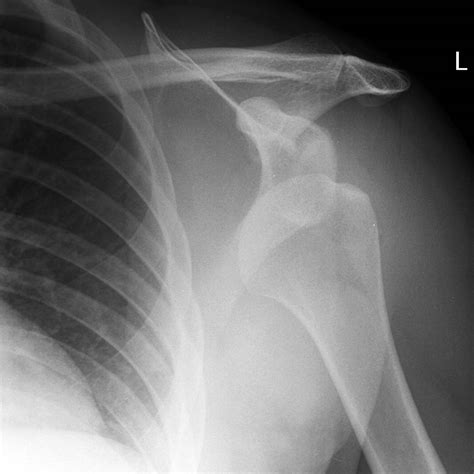

• Detecting fractures: Intense trauma can break the humerus, the glenoid rim, or the acromion. These fractures change the treatment plan significantly.

Hill-Sachs Lesion A small indentation or "dent" on the back of the humeral head, often caused by the bone hitting the rim of the socket during dislocation.

Bankart Lesion A tear or fracture of the labrum (cartilage) at the front of the glenoid socket.

Greater Tuberosity Fracture A small break in the bone where tendons attach, commonly seen in elderly patients with shoulder dislocations.

Shoulder Subluxation A partial dislocation where the humeral head is only partially out of the socket.